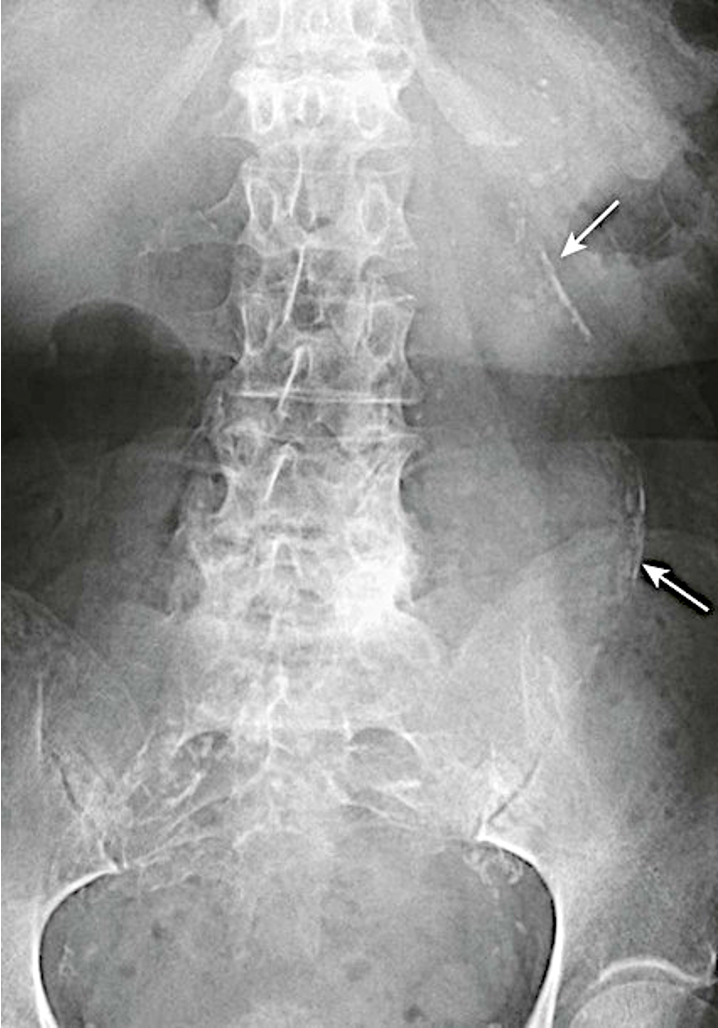

What does splenomegaly look like on XR?

projects below 12th rib

displaces the stomach bubble toward or across the midline